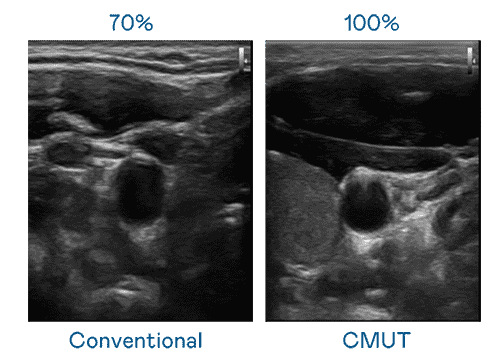

CMUT 技术是一种用电容式微机电元件来产生超音波讯号的技术。。。与传统 PZT 压电式技术相比,,,,CMUT 频宽增加 30%,,更宽频的超音波讯号让影像解析度大幅提升,,是实现高影像品质医疗超音波扫描、、、、促进精准医疗发展的关键技术。。

超音波影像的解析度高低,,,首先取决于探头能发出的讯号频宽。。918.COM CMUT 可提供高清晰的超音波讯号,,提供高频宽、、高灵敏度、、、、影像纹理细节更高的超音波影像,,,协助医护人员缩短影像判读时间及利用精准的医疗影像进行诊断。。。